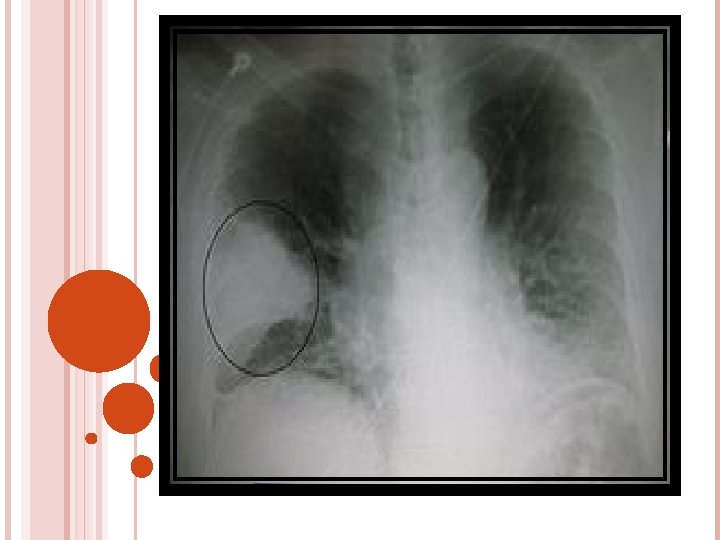

P. AERUGINOSA High in pre existing lung disease / cancer / homograft transplants , burns , tracheostomy , suctioning Diffuse consolidation = chest x-ray Toxic appearance , fever , productive cough , relative bradycardia , leucocytosis Amino glycosides and Antipseudomonal agents – ticarcillin , piperacillin Lung cavitations

DIAGNOSTIC STUDIES History collection , physical examination Chest X-Ray lab Microbiology serology ABG